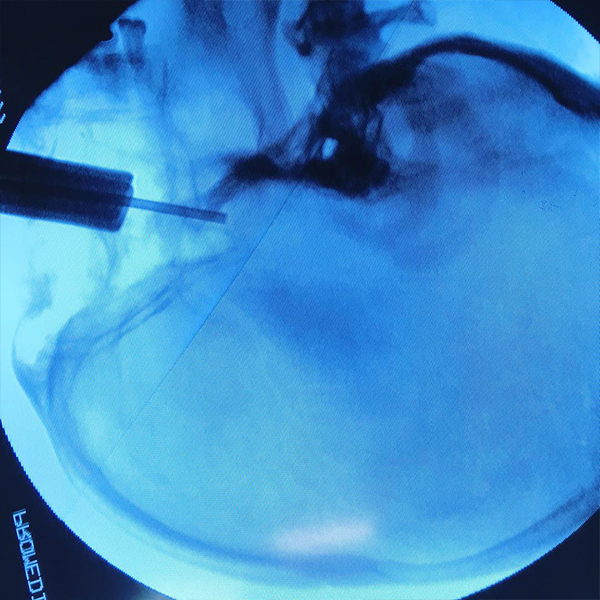

Cirugías de columna

La cirugía de columna permite descomprimir, movilizar los elementos, fijar estructuras vertebrales y sustituirlos. La cirugía de la espalda es una opción a tener en cuenta en el momento en el que tratamientos conservadores no han funcionado y el dolor sigue siendo persistente e impide el desarrollo de una vida normal. Existen diversos tipos de cirugía de espalda:

Cirugía de la columna

lumbar

cervical

torácica